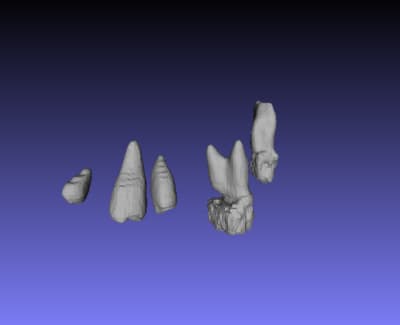

voila mon essaye d'extraction de dent sur Mialite

l'intervalle des densités que j'ai choisie est

Lower Threshold 111

Upper Threshold 1764

mais ce n'est pas reproductible; ça marche pas dans tout les coups